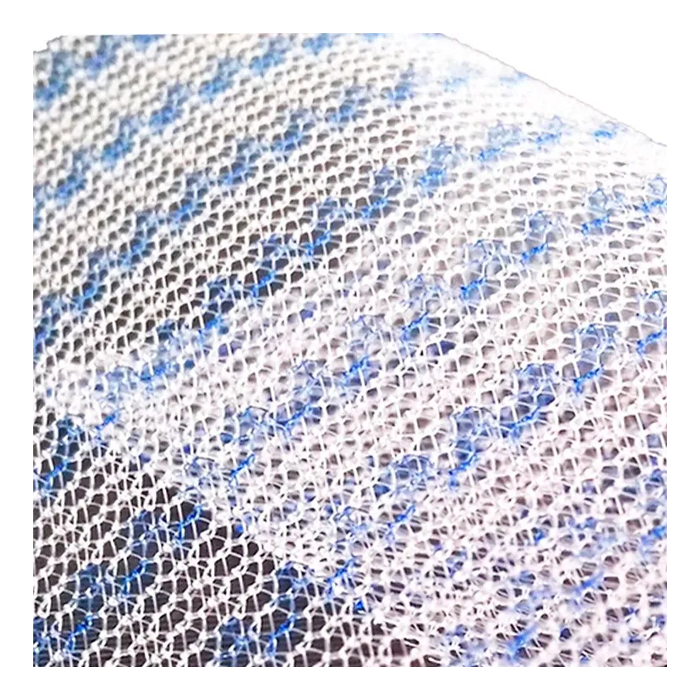

- Оптимальная интеграция с тканями: Особое плетение и структура материала способствуют активному прорастанию соединительной ткани (фиброзной и коллагеновой), обеспечивая надежную фиксацию импланта и формирование единого анатомического комплекса.

- Лёгкость и эластичность: «Лёгкая» модификация сетки обладает сниженной плотностью и массой, что минимизирует ощущение инородного тела у пациента после операции и повышает комфорт в отдаленном периоде.

| Структура | Макропористая, неабсорбируемая (нерассасывающаяся) |